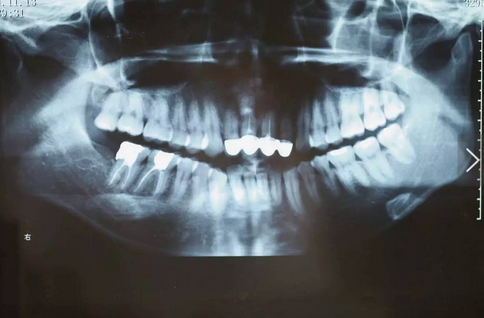

臨床檢查可見12~22烤瓷聯(lián)冠修復,冠邊緣不密合,齦緣外形不協(xié)調(diào),牙齦紅腫,22烤瓷冠崩瓷。根管治療不完善,牙齦根尖部位有瘺管,X線影像顯示11、21根尖有陰影。上頜前突,上前牙修復體舌傾。

治療前曲面體層片

治療前前牙區(qū)X線片